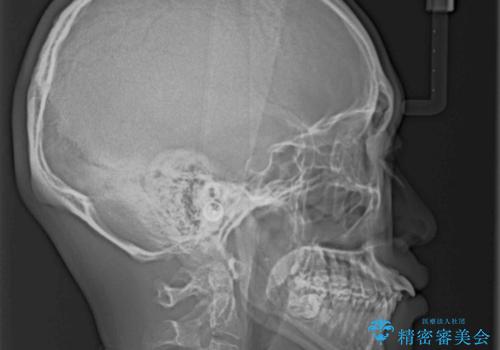

下顎骨が左側に大きく変位しているため、上下の正中位置は極力一致するところをゴールとしました。

上下顎で左右差の大きい抜歯矯正を裏側装置で行ったため、非常に時間がかかりましたが、正中位置も良い位置に改善され、気になっていた突出感も解消されました。